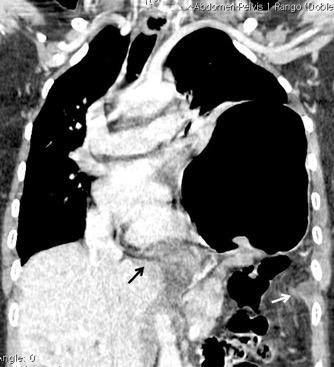

La ocupación del espacio pleural por derrame (o obstrucción aérea) se acomoda con expansión aumentada de la caja torácica, especialmente en eje vertical. La consecuencia es aplanamiento e incluso inversión diafragmática.

Afzal S, Fatima K, Ambareen M. Antenatal ultrasound diagnosis of congenital high airway obstruction syndrome: a case report and review of literature. Cureus. 2019. Thoma R et al. Physiology of breathlessness associated with pleural effusions. Curr Opin Pulm Med. 2015

Wang JS et al. Changes in pulmonary mechanics and gas exchange after thoracentesis on patients with inversion of a hemidiaphragm secondary to large pleural effusion . Chest 1995

Mesotelioma epitelioide